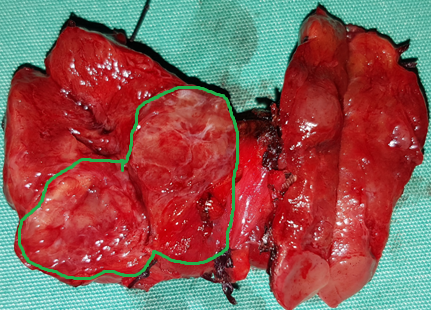

Blue arrow — Parathyroid adenoma. Green arrow — Area of necrosis and hemorrhage (Courtesy Dr. V. Penopoulos)